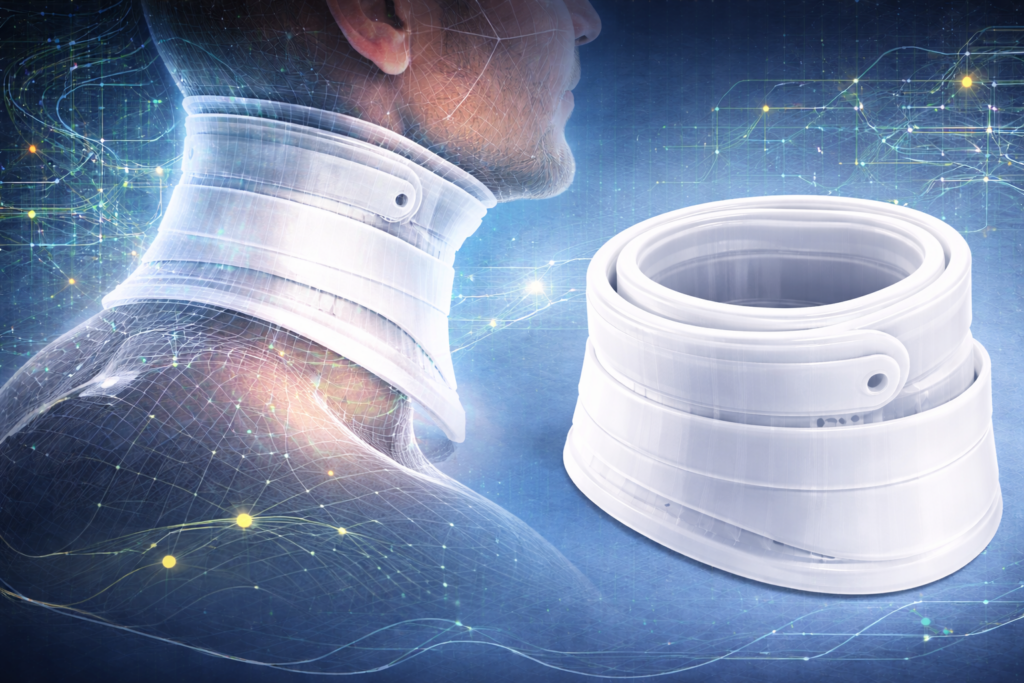

U trećoj fazi istraživanja fokus je bio na primeni prethodno ispitanih metoda na razvoj personalizovane vratne ortoze. Cilj ove faze bio je formiranje ortoze koja prati anatomiju vrata, omogućava lakše postavljanje na telo i može fizički da se realizuje korišćenjem...

U drugoj fazi istraživanja fokus je bio na proveri metoda parametarskog modelovanja i razvijanja površi kroz jednostavniji primer modela ruke, pre njihove primene na složenijoj formi vratne ortoze. Kao osnova korišćen je postojeći 3D model ruke, koji je skaliran prema...

Oblast istraživanja Ergonomska i funkcionalna optimizacija pomagala za imobilizaciju vratne kičme sa fokusom na personalizaciju putem digitalnih tehnologija i samostalnu upotrebu. Tema istraživanja Dizajn i razvoj personalizovane modularne vratne kragne zasnovane na digitalnom modelovanju i unapređenim ergonomskim karakteristikama. Stanje u...